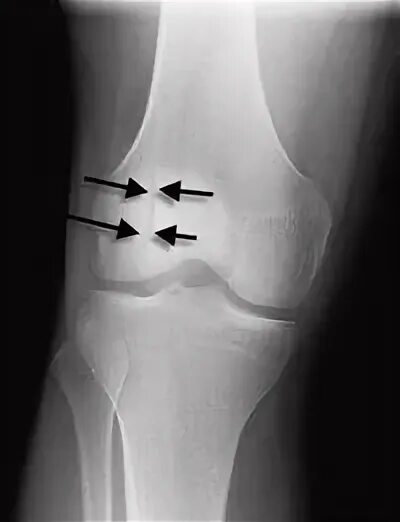

Перелом надколенника код по мкб 10